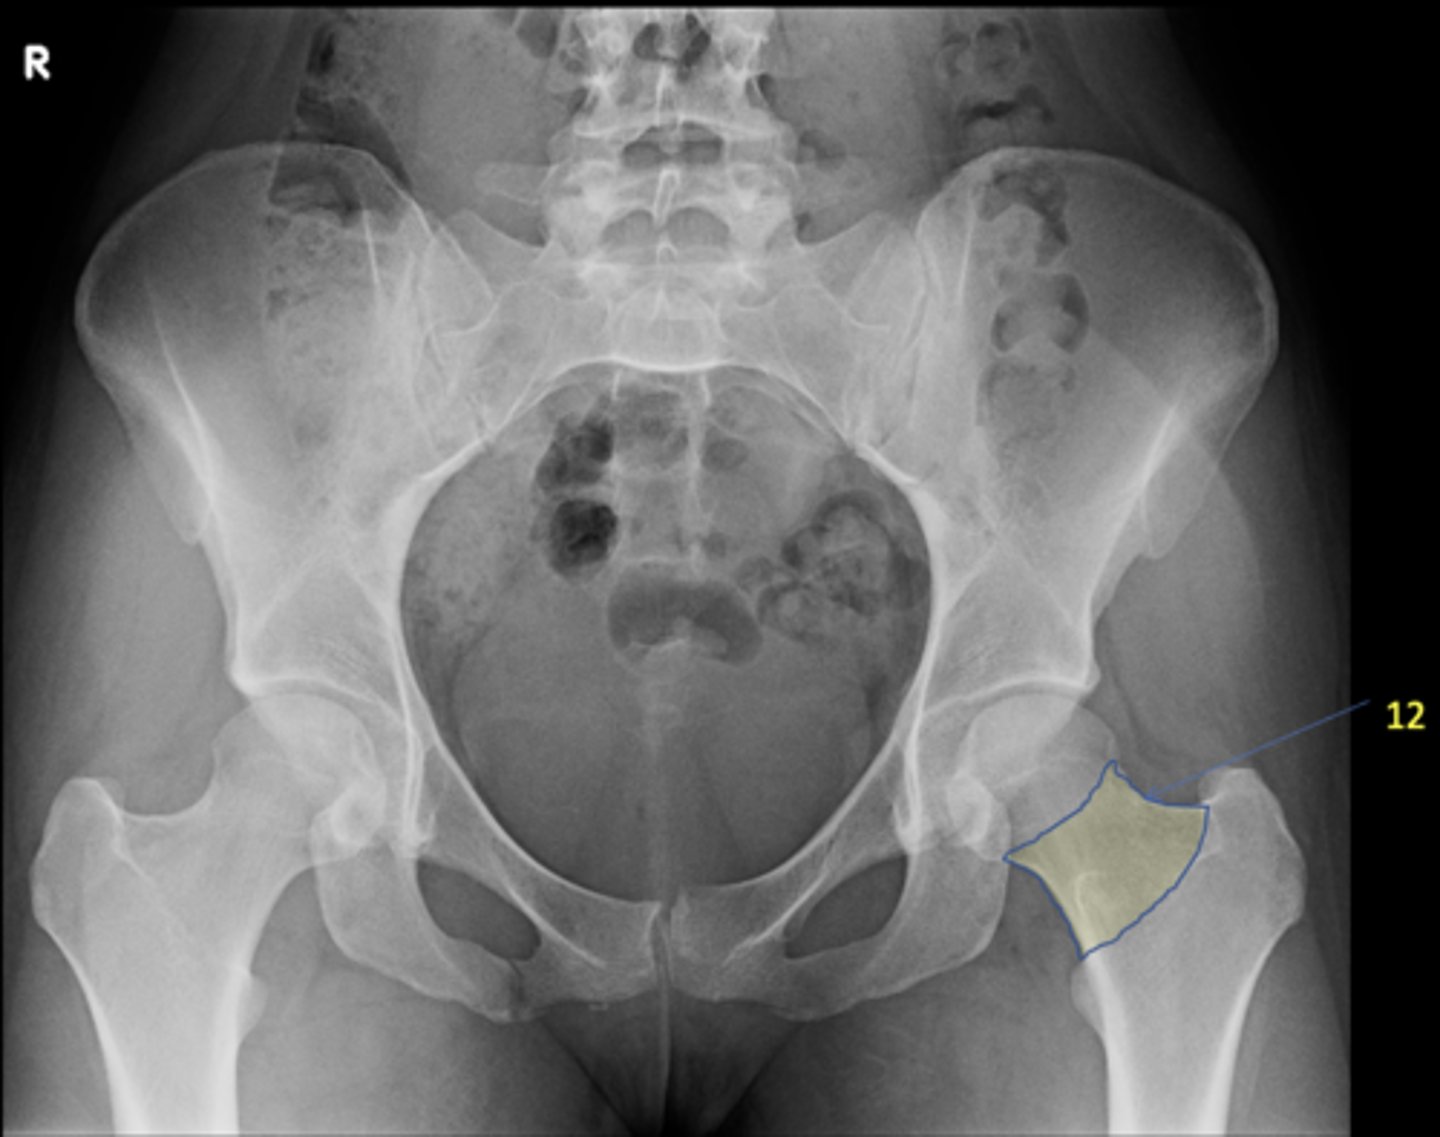

1

New cards

AP pelvis

View?

<p>View?</p>

2

Right lesser trochanter

ID 2

<p>ID 2</p>

3

Left greater trochanter

ID 3

<p>ID 3</p>

4

Right iliac crest

ID 4

<p>ID 4</p>

5

Right iliac fossa

ID 5

<p>ID 5</p>

6

Left anterior superior iliac spine

ID 6

<p>ID 6</p>

7

Right ischium

ID 7

<p>ID 7</p>

8

Left ischial spine

ID 8

<p>ID 8</p>

9

Right fovea capitis

ID 9

<p>ID 9</p>

10

Left obturator foramen

ID 10

<p>ID 10</p>

11

Right posterior superior iliac spine

ID 11

<p>ID 11</p>

12

Left femoral neck

ID 12

<p>ID 12</p>

13

Left anterior inferior iliac spine

ID 13

<p>ID 13</p>

14

Left inferior pubic ramus

ID 15

<p>ID 15</p>

15

S1 tubercle

ID 16

<p>ID 16</p>

16

Left sacral ala

ID 17

<p>ID 17</p>

17

Right femoral head

ID 19

<p>ID 19</p>

18

Kohler's teardrop

ID 20

<p>ID 20</p>

19

Right pubis

ID 21

<p>ID 21</p>

20

Right anterior sacroiliac joint

ID 22 (joint)

<p>ID 22 (joint)</p>

21

Left superior pubic ramus

ID 24

<p>ID 24</p>

22

Right acetabulum

ID 25

<p>ID 25</p>

23

Right intertrochanteric crest

ID 26

<p>ID 26</p>

24

Left ilium

ID 27

<p>ID 27</p>

25

Right ischial tuberosity

ID 28

<p>ID 28</p>

26

Bladder

ID 29

<p>ID 29</p>

27

Ascending colon

ID 30

<p>ID 30</p>